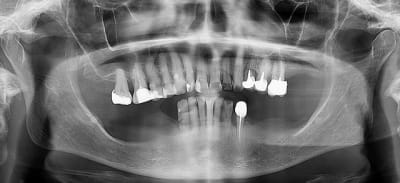

Jusqu'à la photo 3 j’étais pour le traitement CCAM (disque diamanté+foret + empreinte.... nan je déconne pas le disque... humm ...nan).

Au vu de la photo 4 le plan de traitement est purement verbal:

"Votre cas est trop complexe pour moi, allez à la ville ya plein de cador moi je fait que les cas facile." Vu qu'il portera peut-e^tre pas son stéllite ( CCAM toujours) j'aurais trop peur pour mes cerams.

Oui , aller,,on garde le bas qui nous servira de repère pour faire le haut

Je garderai tout ce qui ne bouge pas en bas. Virer des dents immobiles et asymptomatiques c'est sévère ! ;) Un bon bloc d'ancrage pour le stellite.

Pour moi l'usure en haut est purement mécanique.

Par contre, sans implants, durée de vie estimée des 33 / 43 avec un crochet qui tire dessus ?

de toute facon , le stellite ne servira pas de calage , il sera tres tres vite en sous occ . avec un joli crochet qui va flotter , donc autant faire un crochet bien souple .

je pense que c est plus l'occlusion qui finira les canines , sauf si CCAM en bas aussi .

durée de vie illimitée si le stellite est proprement fait et reste fonctionnel.

Il faudra rebaser le stellite s'il se désadapte et en faire un neuf tous les 7/8 ans lorsqu'il est usé.

Je fais beaucoup d'amovible et je n'arrive pas à me persuader que l'amovible détruit les dents supports de crochet. Pour moi c'est une légende urbaine. Les dents bousillées par l'amovible c'est quand l'amovible est faite en dépit du bon sens ou complètement usée et désadaptée.

J'ai vu des dents supports qui se cassaient la figure, c'étaient des dents en bout de rangée chez des patients paro qui auraient suivi le même chemin s'ils n'étaient pas appareillés.

Et des dents supports de crochets présentes après 30 ans de stellite j'en ai vu aussi.